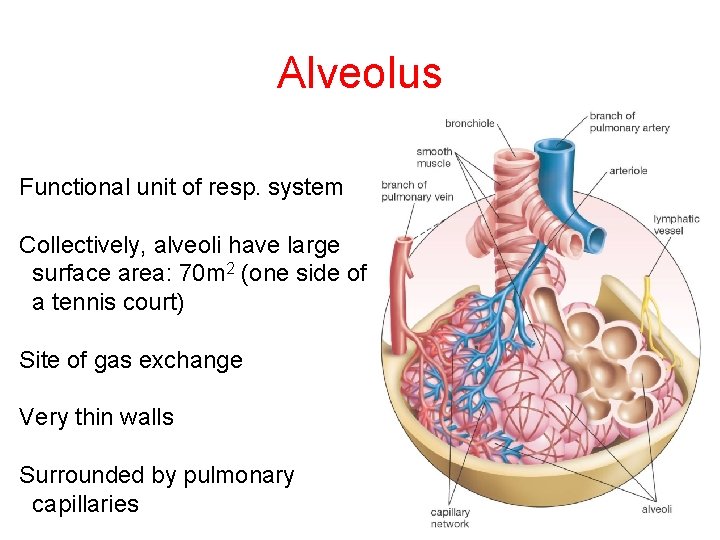

Alveolus Functional unit of resp. system Collectively, alveoli have large surface area: 70 m 2 (one side of a tennis court) Site of gas exchange Very thin walls Surrounded by pulmonary capillaries